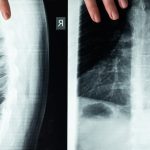

Le bombement discal se produit lorsque les disques intervertébraux, constitués de cartilage, subissent une pression accrue et changent de forme. Cette déformation ne provoque pas toujours des symptômes immédiats. Cependant, elle peut générer des douleurs significatives, notamment durant la nuit, lorsque le corps est au repos. Comprendre cette condition est crucial pour entreprendre un traitement approprié.

Le bombement discal se produit lorsque le disque intervertébral, situé entre les vertèbres, subit une déformation sans craquement ou rupture. Ce phénomène peut engendrer des douleurs, notamment nocturnes, car il exerce une pression sur les nerfs environnants. Cette condition est souvent accompagnée d’une inflammation et d’une gêne importante, altérant la qualité de sommeil et la qualité de vie des individus concernés.

La décompression neurovertébrale se présente comme une solution innovante et non invasive pour ceux qui souffrent de douleurs nocturnes causées par un bombement discal. Ce phénomène, qui se produit lorsque les disques intervertébraux s’élargissent sans se rompre, peut entraîner une compression des nerfs et, par conséquent, des douleurs intenses, surtout la nuit. Pour de nombreux patients, trouver un soulagement reste un défi, d’où l’intérêt croissant pour les techniques de décompression.